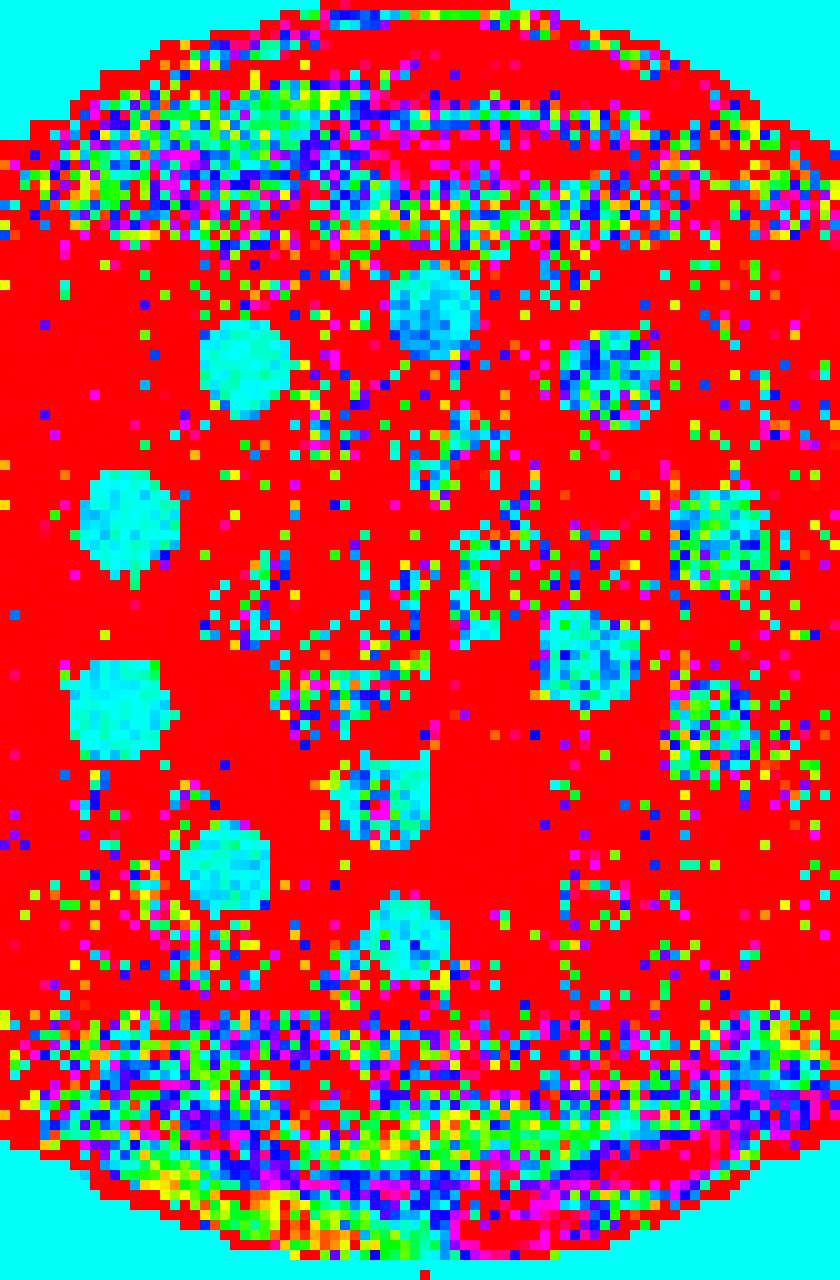

Figure 1 shows a 8×8888\times 8 patch of k-space generated by the patterns with acceleration factor 𝑹=[2,3]𝑹23\bm{R}=[2,3] and Q=72𝑄72Q=72. In this visualisation, each pie slice corresponds to one readout and has a constant area. Hence, the area of each pie corresponds to the number of times with which that k-space position is sampled in the entire acquisition.

Refer to caption

(a) Regular

(b) Treg

(c) Sreg

(d) TSreg

(e) Random

(f) Halton

(g) Legend

Fig. 1: Graphical representation of undersampling patterns for 𝑹=[2,3]𝑹23\bm{R}=[2,3], k-space size of 8×8888\times 8 and number of contrasts Q=72𝑄72Q=72. Legend: each row represents a set of contrasts, grouped together with according to contrast property such as inversion times.